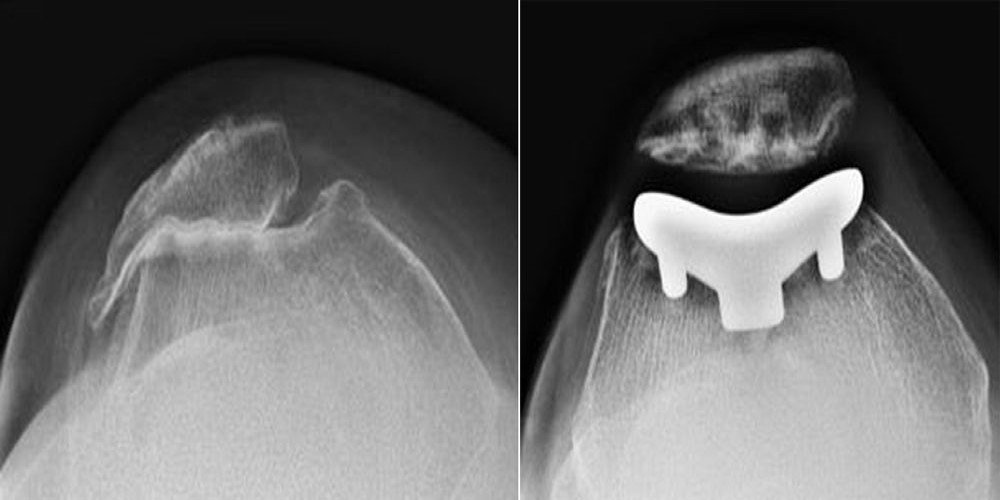

Knee Osteoarthritis An Overview Robert Howells Arthritis Knee learn about the causes, symptoms, diagnosis, and treatment of knee arthritis, a common and disabling joint disease. learn about osteoarthritis, a condition that affects the cartilage between the knee joints and causes pain, swelling,. Find out about the varying knee arthritis symptoms and treatments that. arthritis and knee pain come in many forms. learn about knee. Arthritis Knee.